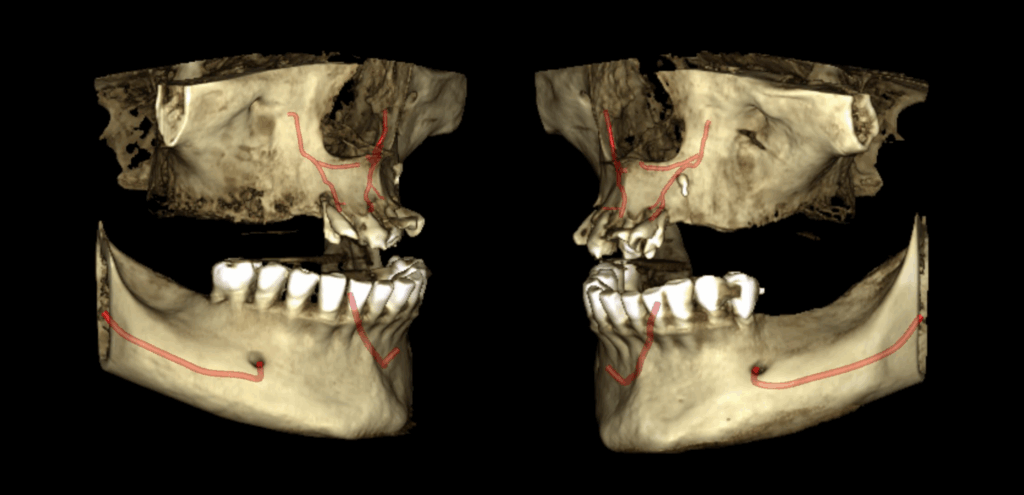

En el estudio complementario mediante tomografía computarizada de haz cónico (TCHC), se identifica la presencia del canalis sinuosus en el maxilar derecho, con trayecto que se dirige hacia la región ósea palatina correspondiente a las piezas 12 y 11. Asimismo, se evidencia un canalis sinuosus en el maxilar izquierdo, que se origina en la pared lateral de la fosa nasal izquierda y se dirige hacia la región ósea palatina y apical de las piezas 21 y 22.

RECONSTRUCCIÓN 3D